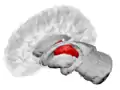

Thalamus

The thalamus (PL: thalami; from Greek θάλαμος, "chamber")[1] is a large mass of gray matter located in the dorsal part of the diencephalon (a division of the forebrain). Nerve fibers project out of the thalamus to the cerebral cortex in all directions, allowing hub-like exchanges of information. It has several functions, such as the relaying of sensory signals, including motor signals to the cerebral cortex[2][3] and the regulation of consciousness, sleep, and alertness.[4]